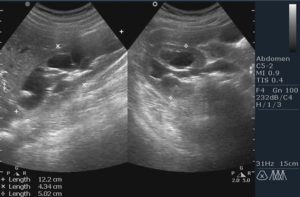

Данное заболевание обычно диагностируется во второй половине срока беременности. Таблица размеров расширения лоханок почек у плода:

| Второй триместр (норма) | Третий триместр (норма) | Патологический размер (гидронефроз) |

| 5 мм | 7 мм | 10 мм и выше |

Уже на 16-18 неделе внутриутробного развития врач может четко визуализировать чашечно-лоханочную систему (ЧЛС) плода с помощью УЗИ. Нормальные размеры лоханки при этом не должны превышать:

- 5 мм – во ll триместре;

- 7 мм – в lll триместре.

- задний и передний размер лоханок (до 33 недели беременности нормой их является размер 4 мм, с 34 — 7 мм);